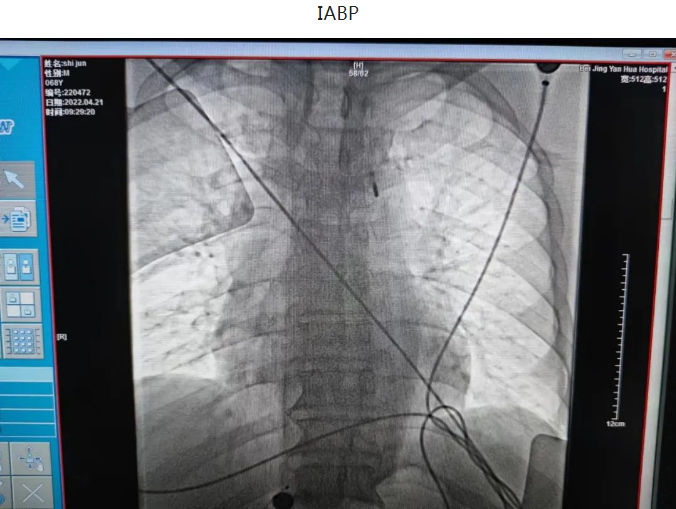

一日凌晨,68岁的石大爷睡眠中突发心前区压榨样疼痛,伴一过性意识丧失,跌倒在地,二便失禁,并胸痛持续不缓解,呼叫120送至我院急诊,心电图提示急性下壁心肌梗死,III度房室传导阻滞,血压74/38mmHg,急诊立即排查新冠肺炎的同时联系我科,秦鹏主治医师立即开通心肌梗死绿色通道,做好防护隔离的同时给予患者静脉溶栓治疗,治疗后患者症状缓解,心电图恢复窦律,抢救成功,后完善冠脉造影提示患者冠脉三支血管病变,右冠状动脉细小,前降支闭塞,回旋支狭窄并可见血栓,李钢主任与患者家属充分交待病情,患者三支血管只剩一支并且是本次心梗的血管,病情危重,需要处理回旋支并尝试开通前降支血管,手术难度及风险较高,患者家属表示理解并要求积极抢救,李刚主任及王志勇、刘丹亮副主任医师给予患者置入IABP(主动脉内球囊反搏)作为保护,反复尝试后给予患者回旋支及前降支闭塞血管进行了治疗,植入冠脉支架,患者转危为安,术后持续IABP辅助,心功能逐渐恢复,抢救成功。

第二日晨,3年前冠脉置入一枚支架的62岁的董大爷干农活时突发咽部紧缩感,伴胸闷不适,持续不缓解,呼叫120送至我院急诊,血压75/56mmHg,急诊考虑急性下壁心肌梗死,心源性休克,急诊立即排查新冠肺炎的同时联系我科,做好术前准备后急送至导管室,冠脉造影可见原支架位于左主干至前降支近段,回旋支消失不见,李钢主任反复尝试后找到回旋支开口,并给予成功重新开通血管,患者血流恢复,症状缓解,但血压持续偏低,考虑患者心源性休克,给予患者置入IABP(主动脉内球囊反搏)作为辅助,患者心功能逐渐恢复,治愈出院。

主动脉内球囊反搏(IABP)是一种机械性辅助循环的方法,其基本原理是将球囊导管置于降主动脉内,外接控制装置,随心脏的舒张和收缩进行充气和放气,以增加心输出量,提高冠状动脉的灌注。